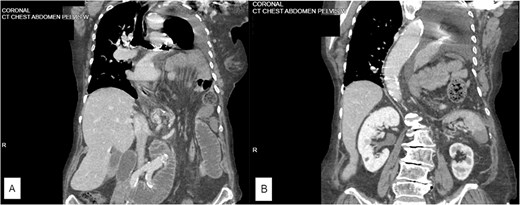

An 82-year-old woman with a prior history of hiatal hernia repair presented to the emergency department with 2 days of worsening abdominal pain and shortness of breath. Her vitals showed hypertension (170/112 mmHg) and oxygen saturation of 90% on room air. On examination, her abdomen was distended and tender to palpation. She exhibited increased work of breathing and decreased breath sounds on the left side. A computed tomography (CT) scan revealed a left diaphragmatic hernia containing small bowel and the splenic flexure of the colon as well as a high-grade small bowel obstruction and hypoenhancement of the spleen (Fig. 1A and B).

(A) Coronal CT scan showing pleural effusion and large left diaphragmatic herniation including a large portion of small bowel as well as splenic flexure of the colon. (B) Coronal CT scan showing herniation into pleural space with an effusion as well as anterior splenic hypoattenuation representing infarction.